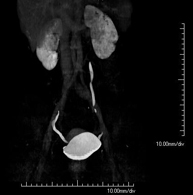

Prova diagnòstica no invasiva que consisteix en l'estudi de les artèries ilíaques i l'aorta abdominal a través de l'obtenció d'imatges d'alta definició anatòmica mitjançant l'ús d'un equip de TC (Tomografia Computeritzada) i de contrast iodat. La qualitat de les imatges permet realitzar reconstruccions en 2D i 3D gràcies a estacions de treball especialitzades en l'estudi arterial. Aquesta prova està especialment indicada com estudi prequirúrgic (mapa vascular) abans d'intervencions percutànies o quirúrgiques d'aorta abdominal, com l'estudi complementari en pacients amb isquèmia de membres inferiors, etc. - Colonoscòpia virtual

Prova diagnòstica no invasiva que consisteix en l'estudi de les artèries ilíaques i l'aorta abdominal amb l'obtenció d'imatges d'alta definició anatòmica mitjançant l'ús d'un equip de TC (Tomografia Computaritzada) i contrast iodat. La qualitat de les imatges permet realitzar reconstruccions en 2D i 3D gràcies a estacions de treball especialitzades en l'estudi arterial. Aquesta prova està especialment indicada com a estudi prequirúrgic (mapa vascular) abans d'intervencions percutànies o quirúrgiques d'aorta abdominal, estudi complementari en pacients amb isquèmia de membres inferiors, etc. - Angio TC arterial d'extremitats inferiors